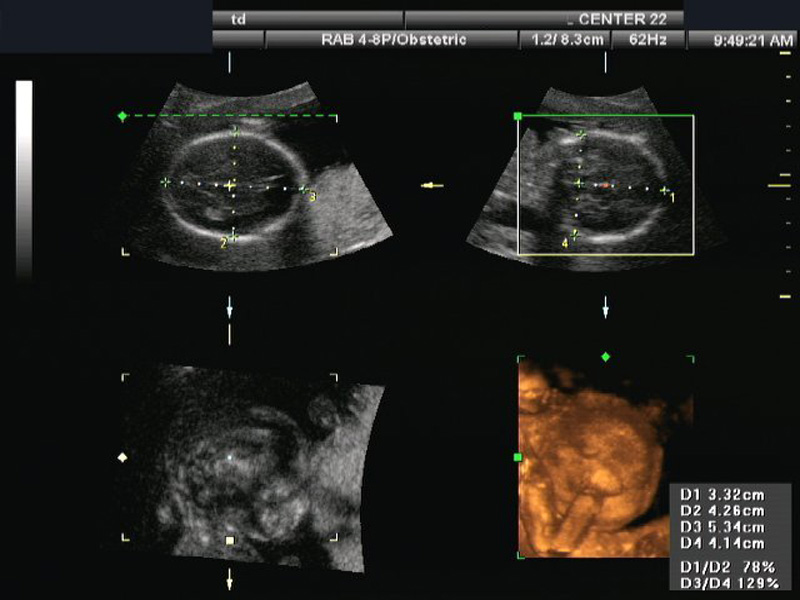

Orthogonal planes of a 3 dimensional sonographic volume with transverse and coronal measurements for estimating fetal cranial volume.